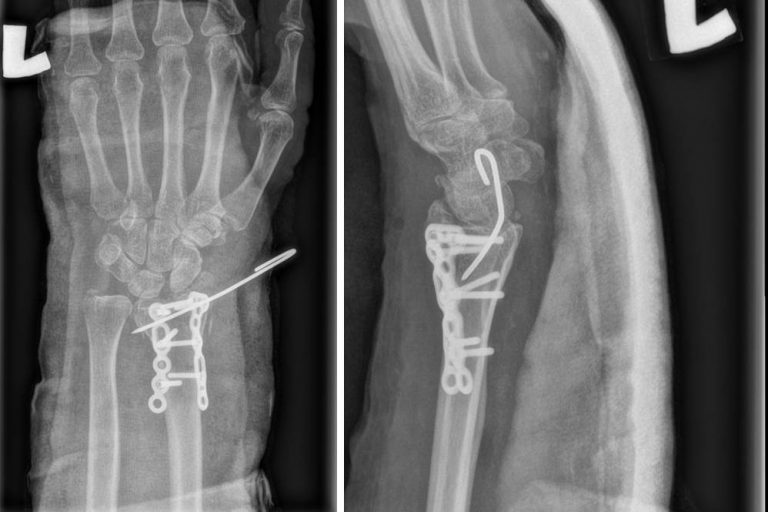

Volar Barton fracture dislocation distal radius Barton Fracture X Ray This type of broken bone can happen. It is also sometimes termed the dorsal type barton fracture to distinguish it. The reverse barton fracture is an articular fracture of the distal radius with dislocation in which the articular surface of the radius remains in contact with the carpus; A barton fracture can be described as volar (more common) or dorsal. Barton Fracture X Ray.

Cureus Volar Barton Fracture and Ulnar Styloid Fracture With Distal Barton Fracture X Ray A barton fracture can be described as volar (more common) or dorsal (less common), depending on whether the volar or dorsal rim of the radius is involved. It is also sometimes termed the dorsal type barton fracture to distinguish it. Barton fractures are fractures of the distal radius. The reverse barton fracture is an articular fracture of the distal radius. Barton Fracture X Ray.